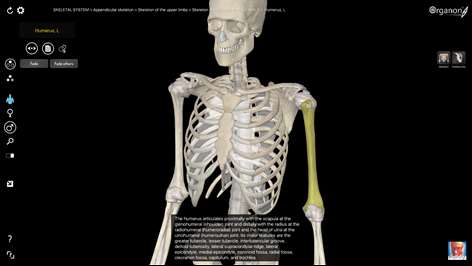

3D Organon Anatomy - Skeleton, Bones, and Ligaments

3D Organon Anatomy - Skeleton, Bones, and Ligaments is a feature-rich interactive anatomical atlas of the skeletal system and connective tissues enhanced with quality anatomy descriptions and texts with frequently encountered clinical correlations.

WHAT IS INCLUDED? This FREE app is part of the full version of the 3D Organon Anatomy available for sale by the Microsoft Store. This version features every bone of the skeletal system and connective tissues. In the full version you can learn human anatomy with over 4000 realistic anatomical models/structures. An all-in-one solution for learning clinical, topographic and systems-based anatomy. The 3D anatomy models can add important cognitive input for understanding the spatial relationship between anatomical structures and features leading to an increased retention of knowledge.